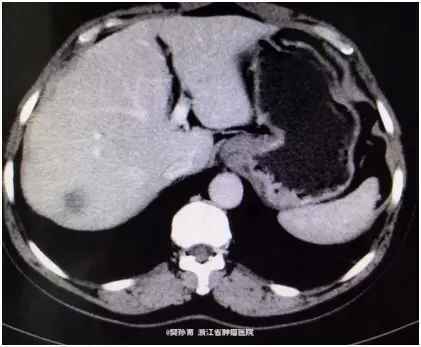

查体:心肺查体阴性,腹平软,无腹壁静脉曲张,全腹无压痛、反跳痛,腹部无包块。肝脏未触及,脾脏未触及,Murphy氏征阴性,肝、肾、脾无叩击痛,无移动性浊音。肠鸣音正常。 肿瘤标志物阴性。 CT表现:动脉期:肝包膜光整,肝脏形态正常,肝右叶可见低密度结节。大小约1.8*2.4 cm。边界模糊。门脉期:病灶强化幅度减低,边界较动脉期清晰。延迟期:病灶仍呈低密度。肝内胆管不扩张,肝门结构清晰自然,胆囊不大,壁光滑,腔内未见明显异常。脾脏、胰腺、胃、腹膜后未见明显异常。